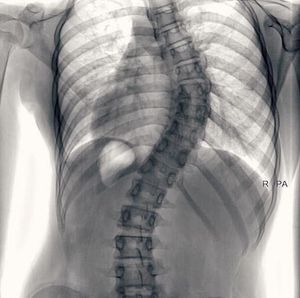

Scoliosis

Combined scoliosis. Treatment is surgery

Scoliosis and tx is surgical

Serpentine scoliosis